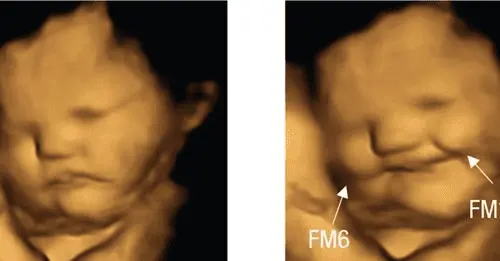

Don't show this to pro-abortionists. Babies in the womb smile over carrots, grimace at kale, new fetus study finds